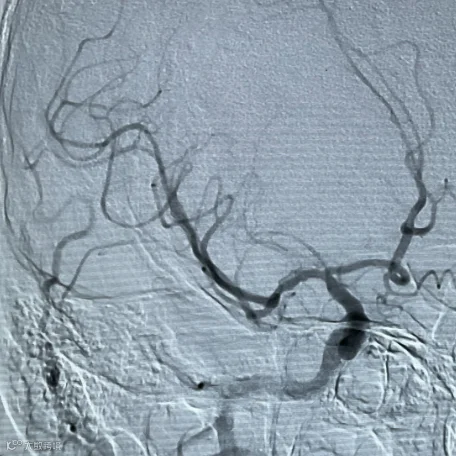

左图:梗死的脑组织

由于颈部没有骨头保护、很脆弱。当用力去按压颈部肌肉时,如果挤压到了动脉血管,则可能出现血管内膜层的撕裂,血液侵入血管管壁内导致壁内血肿,形成动脉夹层。

夹层在动脉血的冲击下越来越大,挤压正常的血管,使动脉血管狭窄甚至闭塞,或形成血栓脱落,导致远端脑血管堵塞而导致脑卒中。